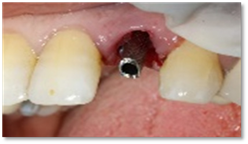

The patient returned for her third appointment, corresponding to the surgical phase of treatment. After disinfecting the incisive-canine area, local anesthesia was administered. The maxillary left lateral incisor (tooth 22) was then atraumatically extracted to preserve the vestibular bone. (Figure 4) Following extraction, the surgical guide was positioned and stabilized, and the drilling sequence was initiated for the placement of a 3.6 mm × 12 mm Biotech implant (Figure 5).

Figure 5: Implant Placement.

After implant placement (Figure 5), the primary stability of the implant was satisfactory (greater than 35N), the provisional abutment was fixed (Figure 6) and a post-operative retroalveolar radiograph was taken for radiological control of the implant and adaptation of the provisional abutment (Figure 7) and finally PMMA resin was placed around the provisional abutment, and the occlusion was checked to ensure that the provisional prosthesis was underbite (Figure 8).

Figure 6: Fixing the temporary abutment to the implant.